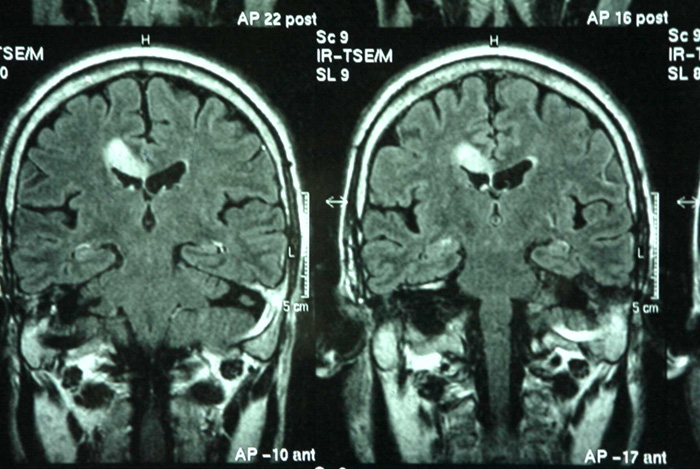

Navegar por la vida requiere equilibrar la emoción y la razón, una labor que realiza la región cerebral conocida como "área 32" de la corteza cingulada anterior. Esta área mantiene el equilibrio emocional mediante la transmisión de información entre las regiones cerebrales cognitivas y emocionales, según una nueva investigación en monos publicada en 'JNeurosci', la revista de la Sociedad de Neurociencia norteamericana.

La regulación emocional saludable requiere la comunicación entre regiones cognitivas, como la corteza prefrontal dorsolateral y las regiones emocionales, como el área 25, también conocida como corteza subgenual. Pero debido a que estas dos áreas están débilmente conectadas, debe haber un intermediario involucrado.

Los investigadores utilizaron trazadores de neuronas bidireccionales para visualizar las conexiones entre la corteza prefrontal dorsolateral, el área 25 y el área 32, un posible intermediario, en los monos rhesus.

La corteza prefrontal dorsolateral se conecta a las capas más profundas del área 32, donde residen las neuronas inhibidoras más fuertes. El área 32 se conecta a cada capa del área 25, posicionándola como un poderoso regulador de la actividad de esta área 25.

En cerebros sanos, la corteza prefrontal dorsolateral envía señales al área 32 para equilibrar la actividad del área 25, lo que permite el equilibrio emocional. Pero en la depresión, el silencio de la corteza prefrontal dorsolateral resulta en demasiada actividad del área 25 y un procesamiento emocional fuera de control.